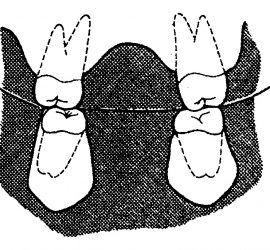

Аппарат представляет собой проволочный нёбный бюгель, который используется для стабилизации положения моляров, после лечения дистализирующими аппаратами, а так же для предотвращения потери места при лечении с удалением зубов. Жёсткая фиксация кнопки Нансе с кольцами создает прочную конструкцию для удержания достигнутого результата лечения.